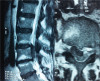

Trauma is a common cause of pneumocephalus, or air in the cranial cavity, and of pneumorrhachis, or the presence of intraspinal air. After spinal surgery, occurrence of pneumocephalus, especially with pneumorrhachis, is extremely rare. We report the case of a patient who developed pneumocephalus and pneumorrhachis after lumbar disc surgery and pedicle screw fixation. There was no cerebrospinal fluid leakage during surgery. On postoperative day 1, the patient complained of headache, nausea, and dizziness. Brain and lumbar computed tomography scans revealed pneumocephalus and pneumorrhachis. With conservative treatment, the patient's complaints resolved within 10 days.